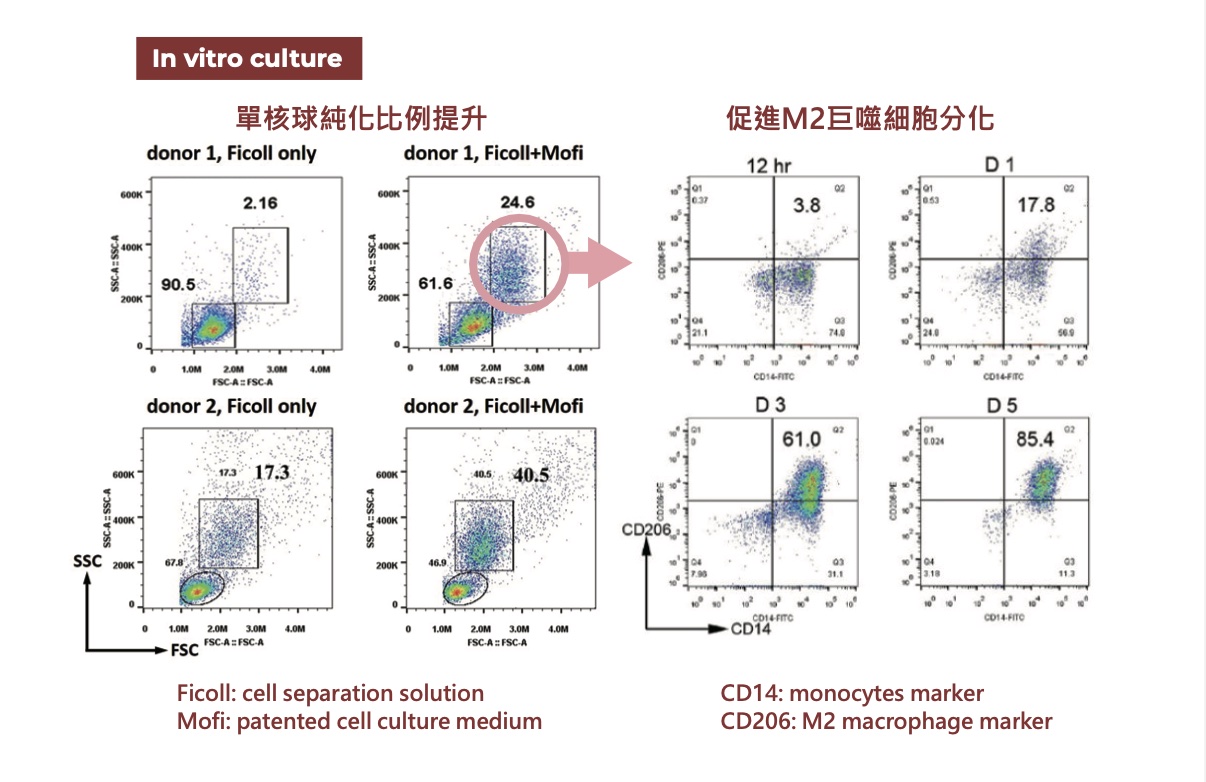

獨家技術提升單核球比例,促進 M2 巨噬細胞分化

研究圖中說明,PCP / AI Cells 技術可提升血液單核球比例,並有效促進其分化為 M2 巨噬細胞。M2 巨噬細胞與抗發炎、組織修復密切相關,對於改善慢性發炎環境與支持組織修復具有重要意義。

另一組圖像則顯示,純化後的 AI Cells 可產生第二型膠原蛋白(Type II collagen),代表其在關節與軟骨相關修復機制上具有應用價值,也呼應療程中「抗發炎+促修復」的核心方向。